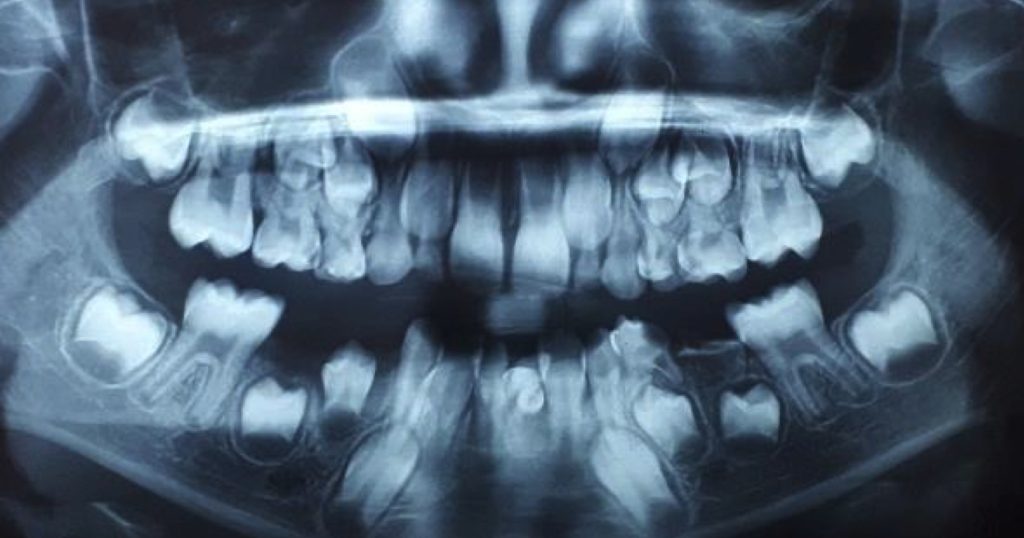

- Métodos de cierre de espacios: Clasifica los métodos en dos categorías principales:

- Mecánica de fricción: Implica el movimiento de los dientes a lo largo de un arco de alambre a través de brackets y tubos, donde la fricción juega un papel significativo.

- Mecánica sin fricción: Utiliza lazos fabricados en el arco de alambre o resortes especializados, que están diseñados para mover los dientes sin la interferencia de la fricción.

- Estrategias de retracción: Detalla las dos mecánicas más utilizadas en la retracción anterior:

- Retracción en dos pasos: Primero se retraen los caninos y luego los cuatro incisivos.

- Retracción en masa: Implica la retracción de los seis dientes anteriores al mismo tiempo.